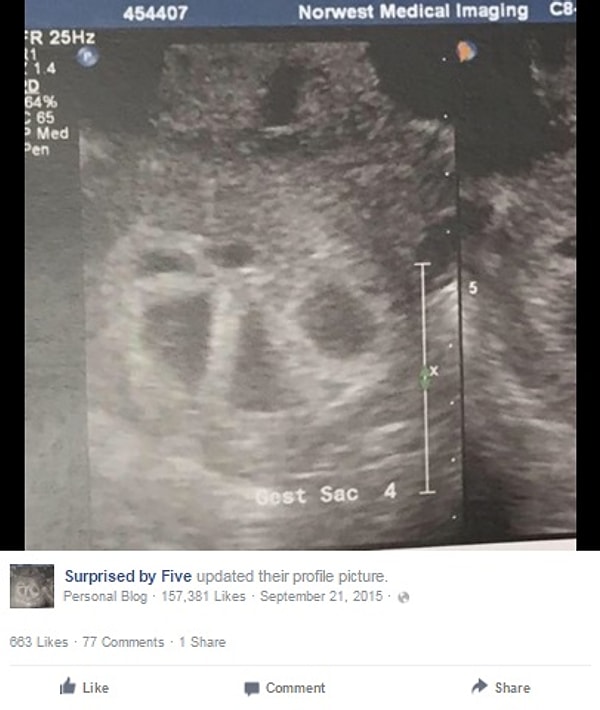

После того, как супруги почти год пытались зачать ребенка, Туччи наконец забеременела в июле. На этом фото срок всего 11 недель.

«Я заподозрила многоплодную беременность из-за резко и быстро поднявшихся гормонов беременности», - написала Ким на своей странице. «Я была рада, что у меня будут близнецы, но к тому, что случилось дальше я была абсолютно не готова».

На ее первом УЗИ врач увидел несколько плодных яиц. А точнее, ПЯТЬ!

«Врач начал считать ОДИН, ДВА, ТРИ, ЧЕТЫРЕ, ПЯТЬ!», - рассказывает Туччи.

«Я правильно расслышала ПЯТЬ? Мои ноги начали трястись и все, что я могла делать – это нервно смеяться».